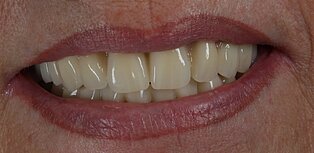

Patientenzufriedenheit